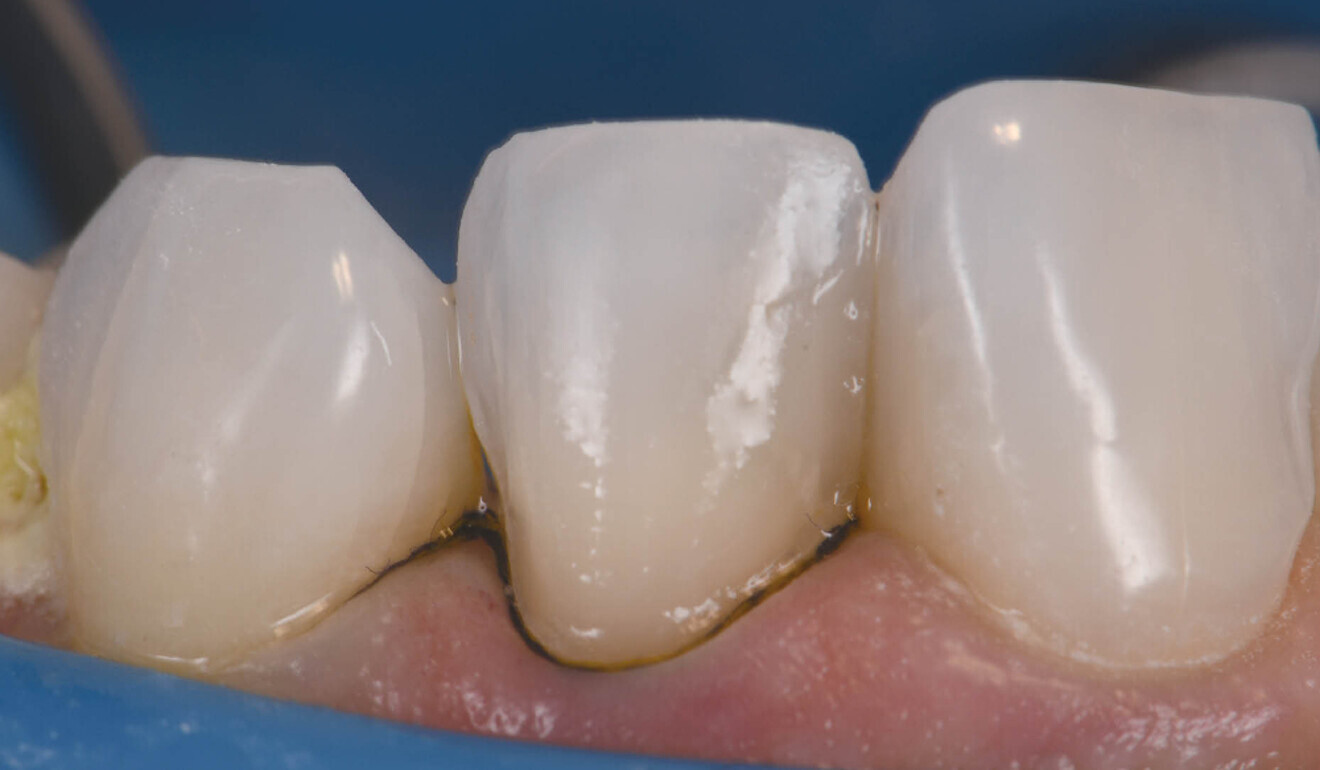

Figs. 2a & b: Veneer preparation of teeth #12 and 22.

The basic body shade was VITA 0M2 with an ingot shade of BL2. The patient was anaesthetised using 1.5 carpules of a 2% lignocaine solution with 1:100,000 adrenaline before affixing a dental dam in a split-dam orientation. The veneer on tooth #12 was sectioned and removed and a minimally invasive veneer preparation completed on tooth #22 (Fig. 2). Partial replacement of the old composite resin restoration was completed on the mesio-inciso-buccopalatal aspect of tooth #12 and the intact segment maintained. Adhesion to old composite was achieved using both microparticle abrasion and a 10-MDP-containing silane coupling agent (CLEARFIL CERAMIC PRIMER PLUS, Kuraray Noritake Dental). The margins were refined, and retraction cord was soaked in an aluminium chloride solution and packed. The preparation stump shades were recorded. The final impressions were taken using both light- and heavy-bodied polyvinylsiloxane in a metal tray. The patient was provisionalised and sent away with instructions to verify the shade at the laboratory at the bisque bake stage. The models prepared by the laboratory verified the minimally invasive nature of the case.